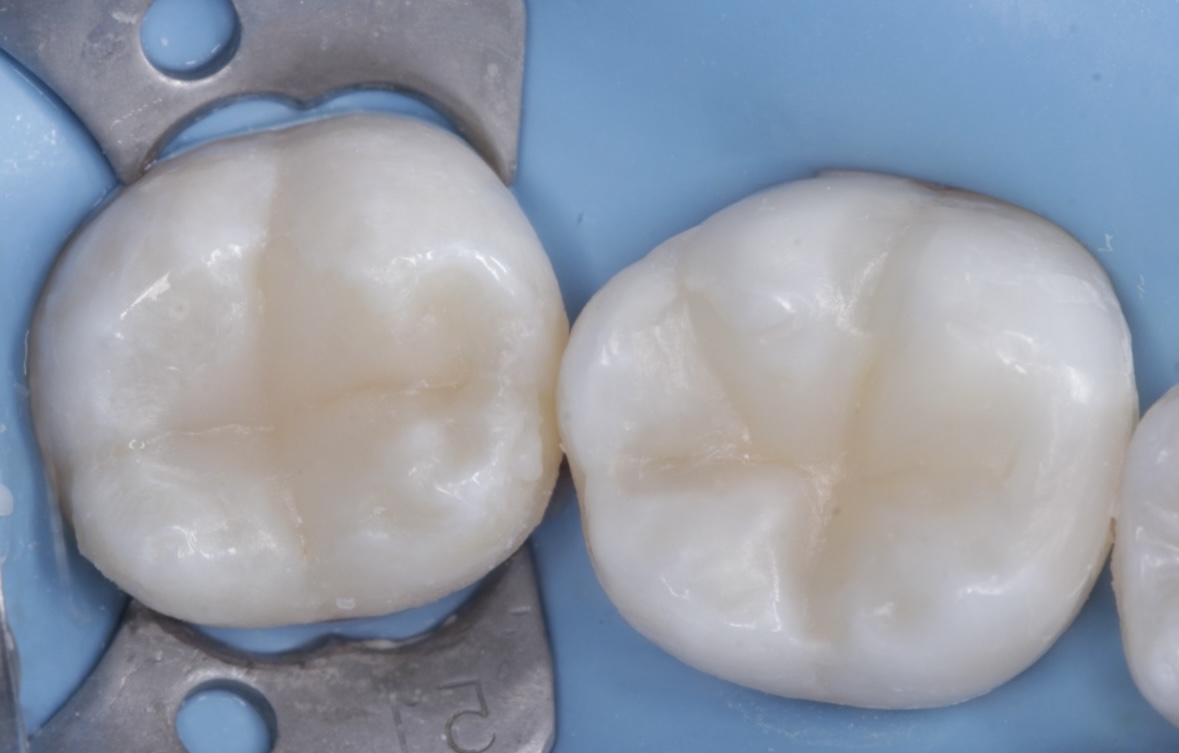

Кейін

Кейін

Кейін